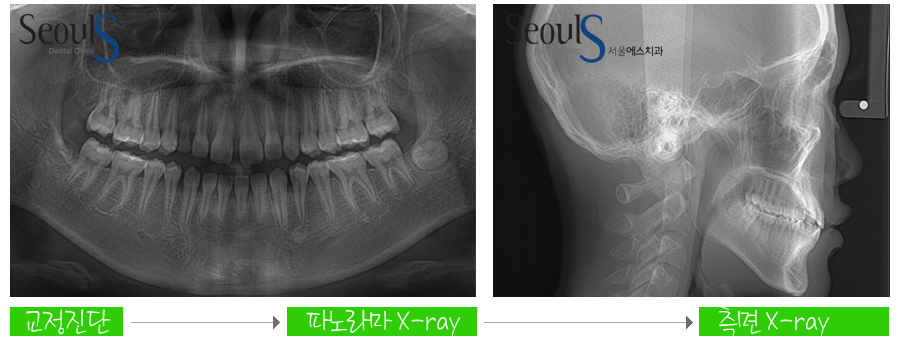

교정 전, 진단을 합니다

교정진단은

파노라마 X-RAY, 측면 X-RAY, 진단 모형 제작 및 분석 후

컴퓨터 교정 프로그램(V-ceph)에 입력합니다

교정 진단 후

환자분에게 가장 좋은 교정방법을 제시해드리고

치아에 교정 장치를 부착해 교정을 진행합니다